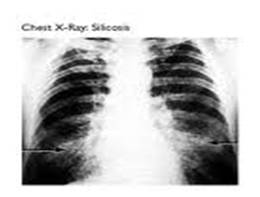

1. Heath surveillance : physical examination, Spirometry, Audiometry, Vision test, Biomarkers (t,t MA in urine, blood Lead) Health effect (Chest X-ray for Silicosis.)

1. Surveillance and prevention of lung disease.(Silicosis)